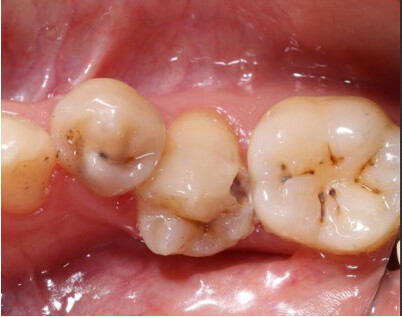

Hình 2: Sâu răng ở bệnh nhân mang thai

Phụ nữ mang thai thường ăn nhiều bữa nhỏ, tạo điều kiện cho axit tồn tại trong miệng gây sâu răng. Đặc biệt, trong thời gian ốm nghén, việc chải sạch răng hàm bên trong trở nên khó khăn hơn. Bên cạnh đó, thói quen ăn vặt để chống buồn nôn và việc vệ sinh răng miệng không đúng cách cũng làm tăng nguy cơ sâu răng. Môi trường pH trong miệng thay đổi và tính chất nước bọt bị biến đổi, tạo điều kiện thuận lợi cho vi khuẩn xâm nhập và tấn công răng lợi.